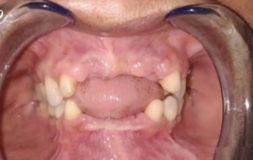

WHEN IS DENTAL CROWN NEEDED?

Dental crowns are used as caps on missing or fractured tooth to protect the life of your teeth. Dental Crowns are needed to:

• Protect or restore a tooth from fracturing due to accident or trauma

• Replace a tooth which is too large for a filling

• Get a cap over Implant placed

• Restore the tooth on which RCT was performed

• Cover discolored, misshaped or badly formed tooth

• Require a bridge in that case crowns are a must